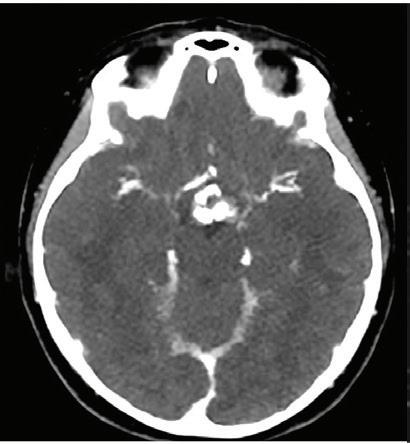

Unenhanced cranial CT of a 55-year-old patient in conventional image and virtual monoenergetic image reconstruction at 40 keV. Note that gray-white matter differentiation is clearly superior in 40 keV images.

Conventional Virtual monoenergetic 40 keV Clinical case collection